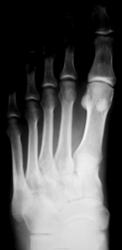

Травма.  Пациент направлен на рентгенографию стопы.

Перелом основания 5 плюсневой без смещения?

Похоже.